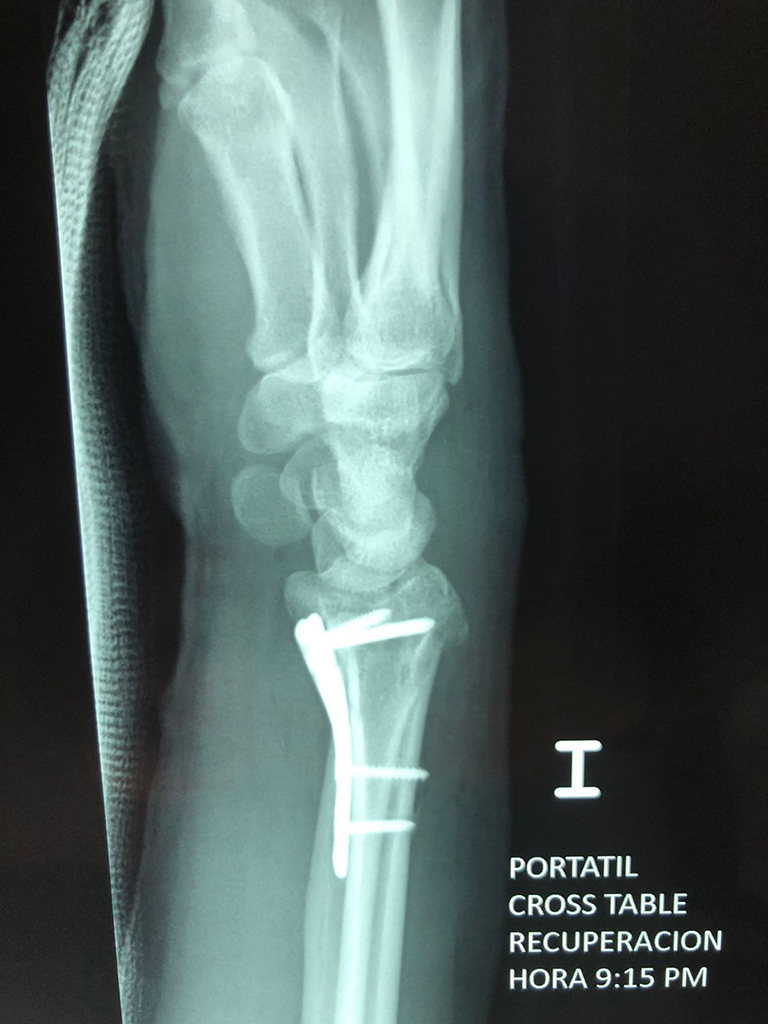

Cirugías de Húmero - Cirugías de Muñecas y Manos

Los procedimientos más comunes en cirugía de la mano son aquellos destinados a reparar traumatismos, incluyendo lesiones de tendones, nervios, vasos sanguíneos, y articulaciones; huesos fracturados; y quemaduras, cortes, y otros daños de la piel.